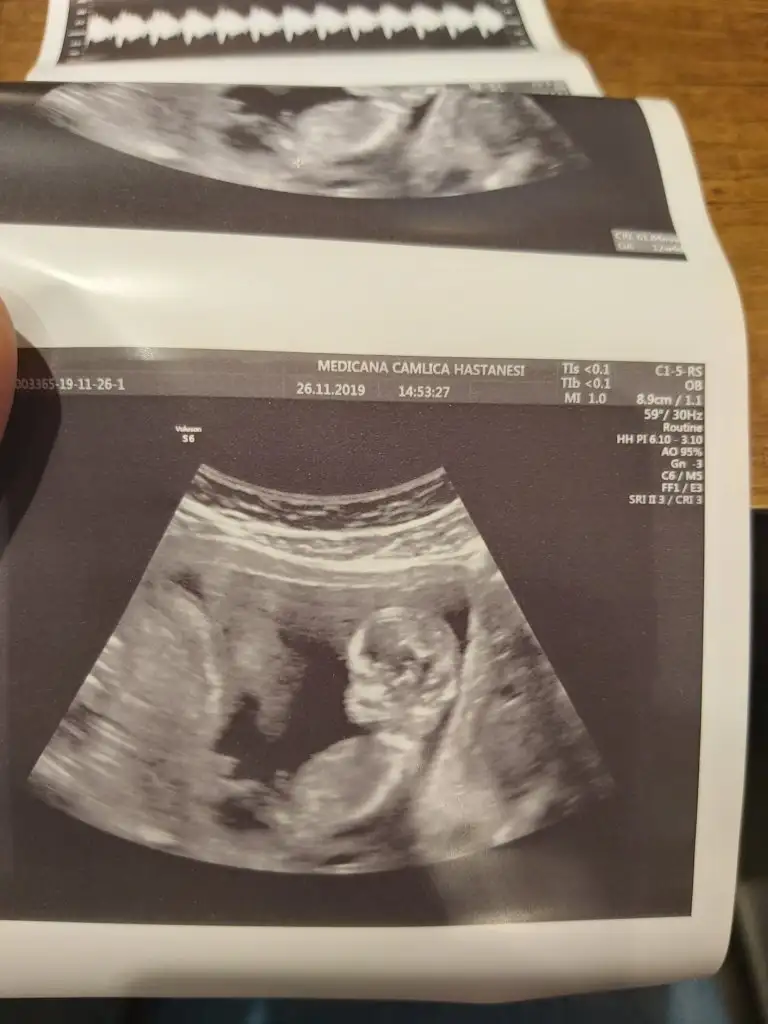

Kaçıncı hafta canım , çok tatlış ya:) maşallahKizlar bebis fotosuyla geldim

Eki Görüntüle 2559113

Doktoru soranlar olmuştu medicana dr.hüseyin arık herşeyi sordum gönül rahatlığıyla güler yüzle gayet iyi bir dr devam edicem doktorumu buldum çok şükür tavsiye ederim dr çok önemli sizi dinliyor motive ediyor.